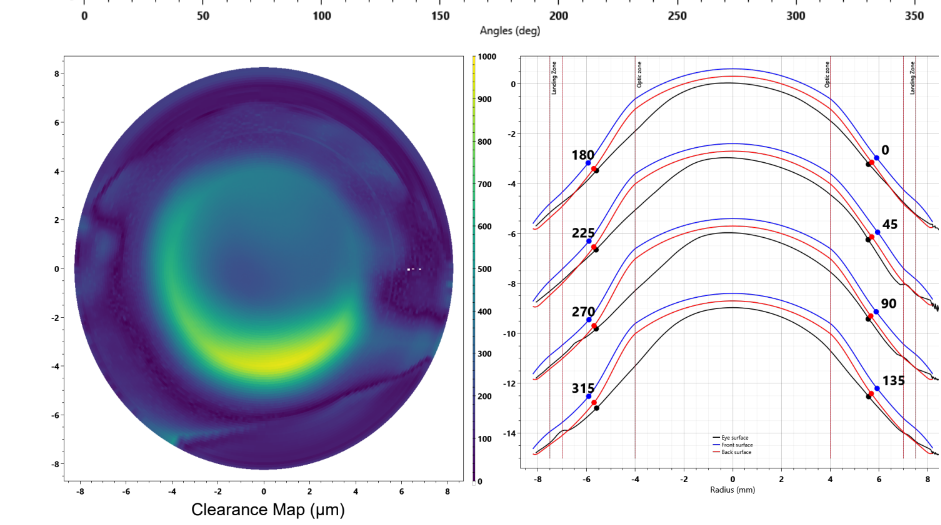

At a scleral lens consultation, we will first learn and discuss your eye health history, take profilometry and topography scans, and discuss your needs. If you are new to scleral lenses, we will place a “demo” scleral lens on your eye(s) to check the vision potential of your eyes, as well as to see if your eyes feel better if your condition is related to dry eyes. If we determine that you are a candidate and proceed with scleral lenses, our doctor Dr. Seif then orders a unique, custom designed lens and adjusts it until the most optimal vision and fit is achieved.

For established wearers, we would assess your current prescription and utilize anterior segment OCT to assess the fit of your current lenses. We may also run aberrometry measurements to see if you would benefit from higher-order aberration correction. We would determine if your current lens design is appropriate healthwise, or if you would benefit from a different lens design.

When customizations are needed or when conventionals fall short. Includes scan-based, freeform, and EyeFitPro (impression molding). 40,000 data points are collected to create a custom fit lens.

For the ultimate precise fit and full customization options utilizing impression molding (EyePrintPro). 80,000 points of data are collected to create a truly unique scleral lens.